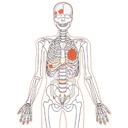

| Features | 1.Radiology absorption and HU number approximate to human body 2. Main joints have close-to human articulation 3. Phantom can be disassembled into 10 individual parts |

| Case / Pathology | Refer to PDF( Anatomy and Pathologies) |